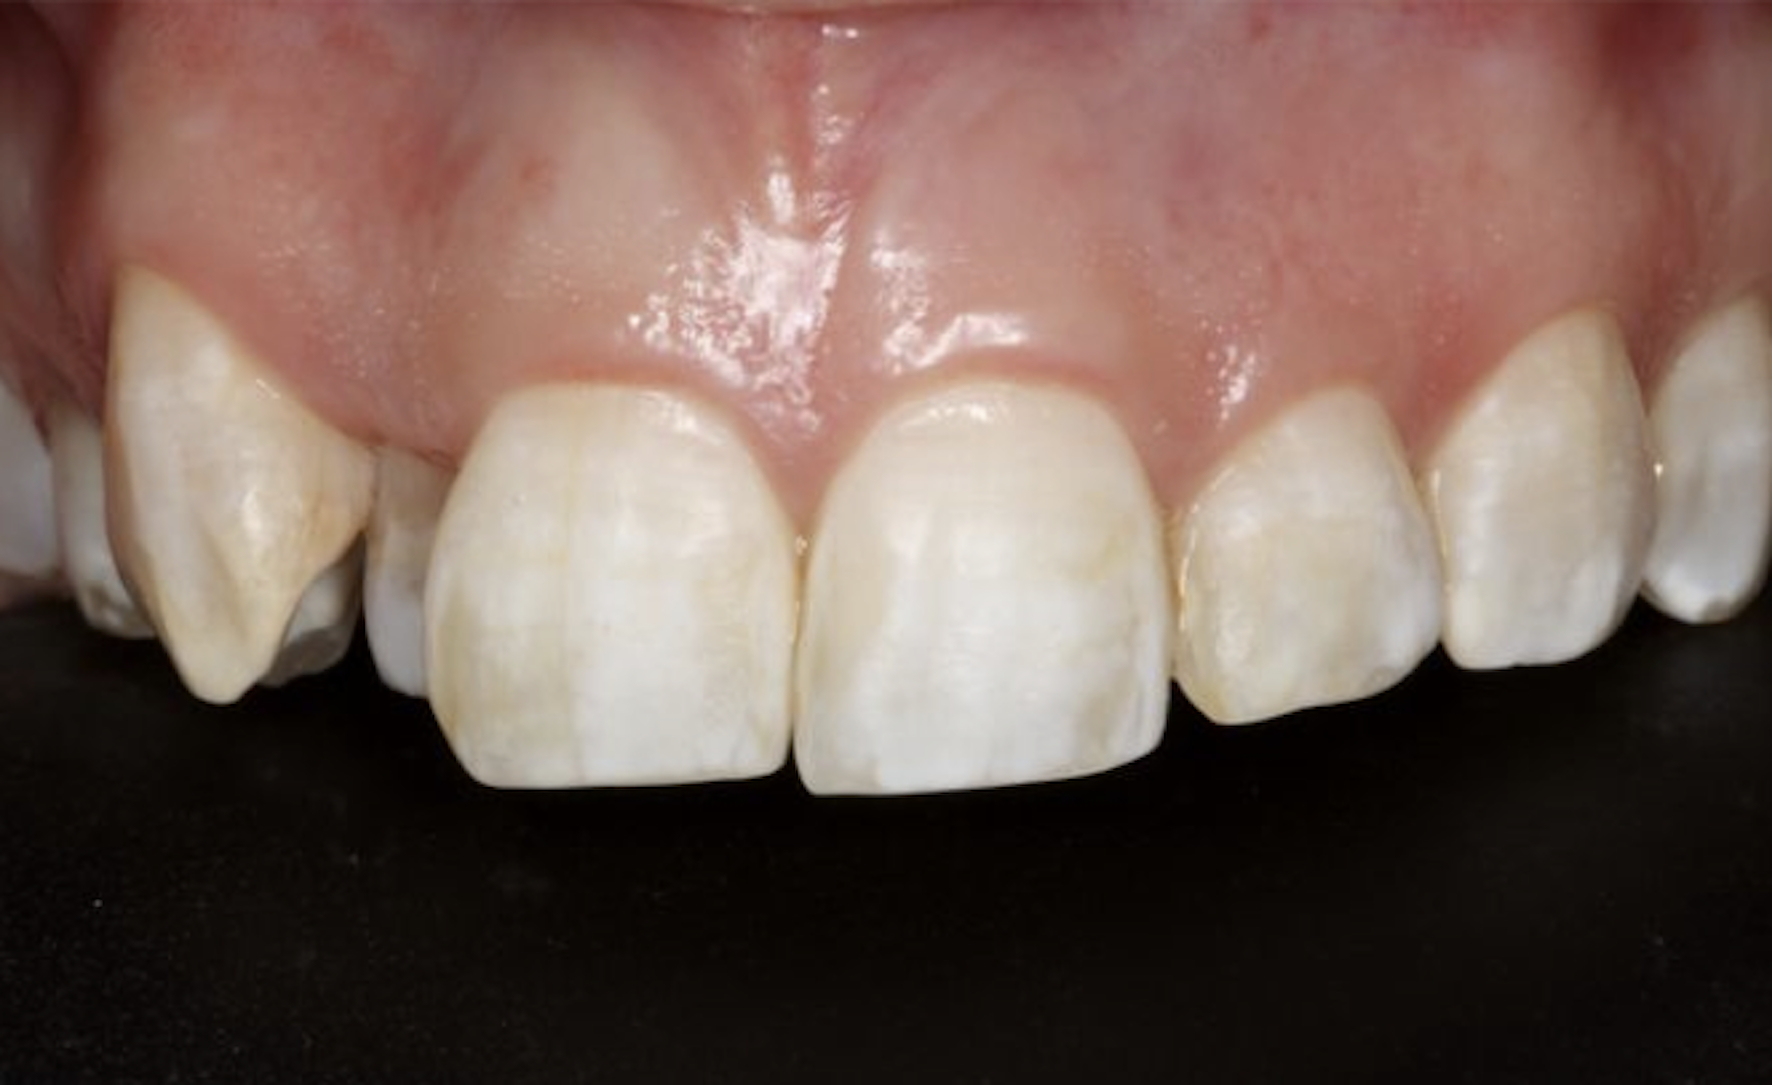

The generalized presence of stain, particularly on anterior teeth, provides an unaesthetic appearance with a negative impact on the patient. The aim of this paper is to report a case of severe chromatic alterations treated with enamel microabrasion associated with infiltration of low-viscosity resin. The intense brownish pigmentation and white spots of fluorosis lose their whitish appearance and look similar to sound enamel. This association of techniques, which might be an alternative to white-masking of intense pigmentation, showed optimal aesthetic results.